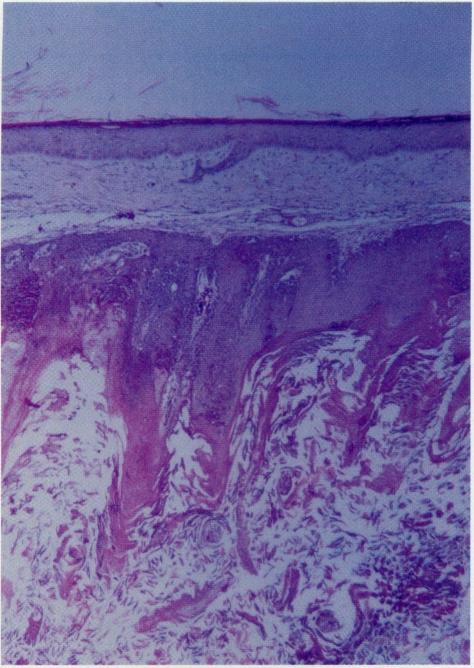

We report 25 cases of skin neoplasm observed among 30 Long Evans rats serving as controls in a psychosocial behavioral study conducted in the Vivarium at Charles R. Drew University, Los Angeles, CA. The animals were 10 weeks old at the beginning of the study. All the skin tumors developed at 18 to 26 months of age and slowly enlarged over a period of 9 months. Multiple nodules occurred in 8 males and 6 females. None of the tumors regressed. The tumors were located around the hind leg and dorso-medial area and measured 1 to 2 cm. Physical examination revealed firm well demarcated dermal masses. Most of the tumor nodules were intradermal, and some had a central ulcerated or keratin-filled core. Microscopic examination performed on some of the tumors showed findings of classic Keratoacanthoma, whereas others showed histologic features suggestive of squamous cell carcinoma. These findings indicate a high rate (83%) of spontaneous skin neoplasms among aging Long Evans rats. To our knowledge, such a high rate of skin neoplasms in aged rodents has not been described in the literature. Furthermore, further studies should be undertaken to confirm these findings and to assess whether these rodents might serve as a model for studying the alterations in the immune system with aging.

在加利福尼亚州洛杉矶市查尔斯·R·德鲁大学动物饲养所进行的一项社会行为学研究中,我们在30只作为对照的长 Evans 大鼠中观察到25例皮肤肿瘤。研究开始时这些动物为10周龄。所有皮肤肿瘤均在18至26个月龄时出现,并在9个月的时间里缓慢增大。8只雄性和6只雌性出现了多个结节。没有肿瘤消退。肿瘤位于后腿周围和背内侧区域,大小为1至2厘米。体格检查发现边界清晰的坚实皮肤肿块。大多数肿瘤结节位于真皮内,有些有中央溃疡或充满角蛋白的核心。对部分肿瘤进行的显微镜检查显示为典型的角化棘皮瘤表现,而其他肿瘤则显示出提示鳞状细胞癌的组织学特征。这些发现表明老年长 Evans 大鼠的自发性皮肤肿瘤发生率很高(83%)。据我们所知,文献中尚未描述老年啮齿动物如此高的皮肤肿瘤发生率。此外,应进行进一步研究以证实这些发现,并评估这些啮齿动物是否可作为研究衰老过程中免疫系统变化的模型。